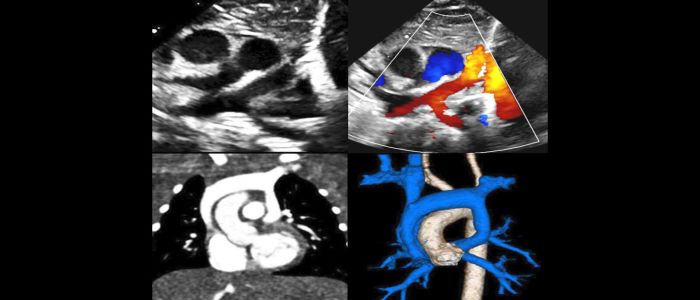

This three-day symposium is designed to provide a deeper understanding of the anatomy, clinical aspects, imaging, and management of patients with congenital heart disease. The symposium will include case discussions, didactic seminars, anatomic and imaging correlations, and discussions of multimodal imaging to illustrate the impact of cardiac imaging on treatment, diagnosis, and management of patients with congenital heart disease. Prices:MD, PhD, DO, PharmD: USD 785.00,Residents, Sonographers, RN, NP, PA: USD 775.00Venue details: San Antonio Marriott Riverwalk, 889 East Market Street, San Antonio, Texas, 78205, United States Date and time: On Thu, 22 Oct 2026 07:00 to Sat, 24 Oct 2026 12:00